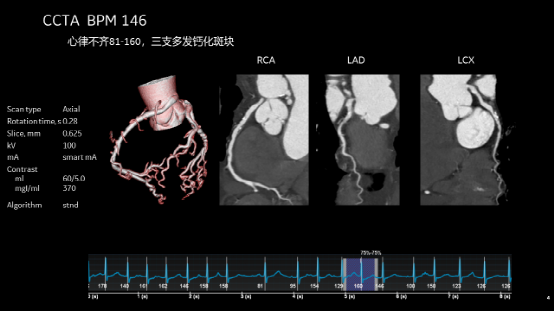

无限制1-Beat 1-Stop心脏成像

在任何心率和心律条件下,一次对比剂注射、 一个心动周期内就可以获得心脏的冠脉解剖信息、斑块成分信息

RCA右冠状动脉多发软斑块并管腔轻度狭窄